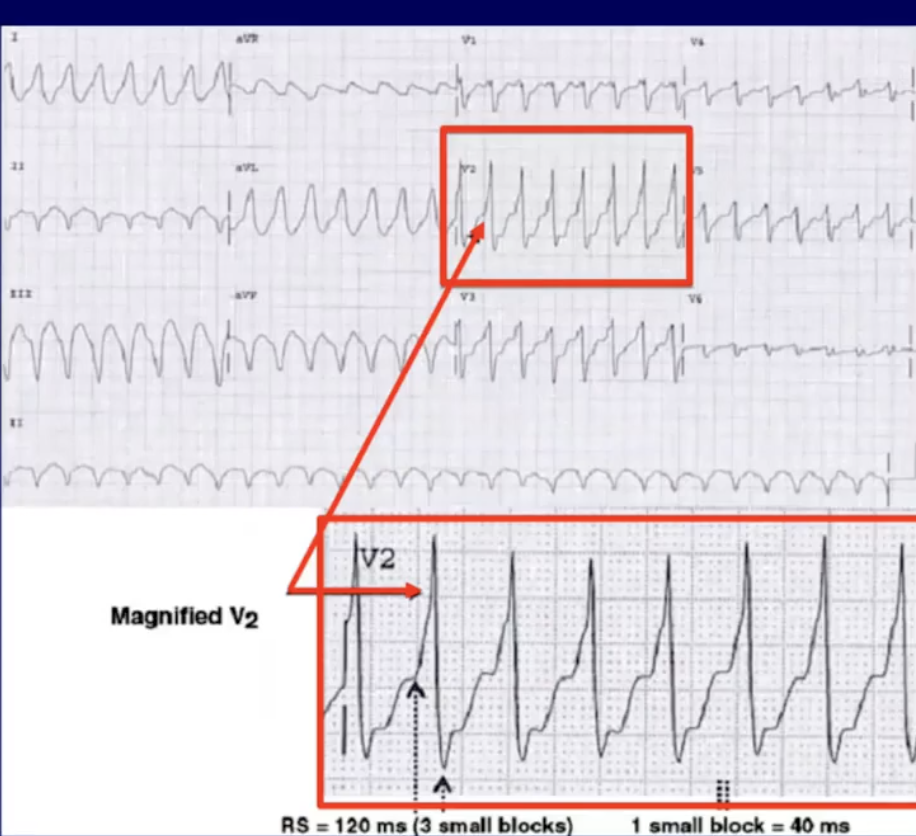

Tiêu chuẩn 2: Khoảng cách dài nhất RS (đầu sóng R và điểm song nhất sóng S) chuyển đạo thành ngực > 110 ms